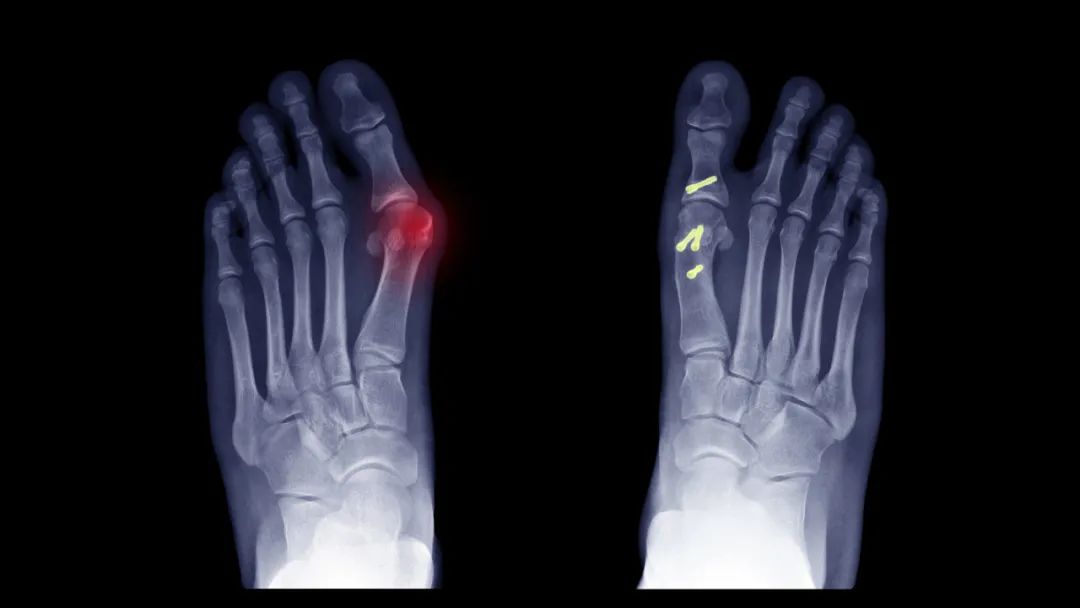

拇外翻到底是什么病?它和穿高跟鞋的关系是?男性会患病吗?今天就来好好聊聊“拇外翻”那些事。拇外翻是指拇趾基底部关节出现骨性突起,拇趾会偏向第二趾。研究发现,65岁以内的成年人患病率约23%;65岁以上患病率更高,达到36%;而女性成人的患病率大约30%。

但一些女性在穿严重压迫脚趾趾甲的鞋时,出现拇外翻,一些男性穿合脚的鞋,也出现明显拇外翻。因此,鞋很可能是加重了拇外翻,却不是拇外翻的根本病因。当甲板侧缘刺穿侧方甲襞并穿入皮肤,从而引起异物反应和继发感染时,我们称为内生甲,或者嵌甲。大脚趾最常见,其特征性表现包括疼痛,水肿,渗出和肉芽组织增生。诱发因素包括不合脚的鞋子、甲板侧缘过度破裂、先天畸形等。

很多人认为拇外翻角度越大,越需要手术治疗。实际上不是这样的。拇外翻手术治疗的适应症是:明显的疼痛,甚至行走困难,而不只是看X线片上的外翻角度。关于拇外翻的手术方式至少有150种之多,具体如何手术要由专业的骨科医生决定,有条件可以选择专业的足踝外科专家。